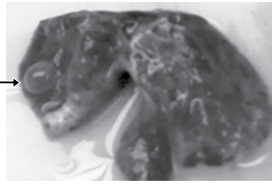

Recém-nascido de termo, filho de mãe primigesta jovem, teve anoxia perinatal durante o parto normal, por período expulsivo prolongado, nascendo com Apgar 1/3/6. Durante as manobras de reanimação, o médico pediatra, ao ventilar a criança, causou barotrauma, pneumotórax por ruptura de bolhas subpleurais, atelectasia pulmonar, piora da anoxia e óbito. A figura mostra o pulmão esquerdo atelectásico, com as tais vesículas subpleurais.

Por parte do médico pediatra, é mais provável que